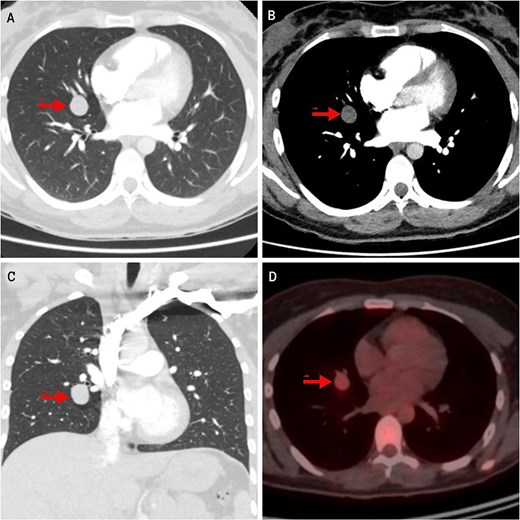

In the evaluation of her dyspnea, a chest computed tomography (CT) angiography was performed, ruling out pulmonary embolism but detecting a homogeneous, well-circumscribed pulmonary nodule measuring 19 mm in the middle lobe (ML). On fluorodeoxyglucose positron emission tomography (FDG-PET), the lesion showed mild hypermetabolism with a standardized uptake value (SUV) of 2.8 (Fig. 1). A low-grade NET was suspected. Two transbronchial biopsies were inconclusive. Serum chromogranin A and 24-hour urinary 5-hydroxyindoleacetic acid (5-HIAA) levels were elevated, indicating a functional NET.

Imaging findings of the pulmonary carcinoid tumor. Contrast-enhanced chest CT. (A, B) Axial views (lung and mediastinal windows); (C) Coronal view (lung window); (D) FDG-PET scan. The arrow indicates a well-circumscribed, round lesion measuring 16 × 19 × 17 mm, with soft tissue density, centrally located in the medial segment of the right middle lobe, and showing mild hypermetabolism on image (D).